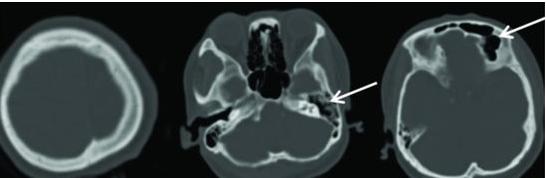

Dyke-Davidoff-Masson综合征

Dyke-Davidoff-Masson综合征是一种由于在胎儿期或生后早期脑损伤所致的少见病。

可发生于各年龄阶段如儿童、青少年及成人,男性发病率较高。

临床特征为癫痫、面部不对称、对侧偏瘫以及智力发育延迟,感觉障碍、学习及语言障碍、精神异常等表现也可出现。

影像表现为一侧大脑萎缩,同侧侧脑室扩张、颅骨增厚、鼻窦及乳突窦增大、岩骨嵴和蝶骨大翼抬升。